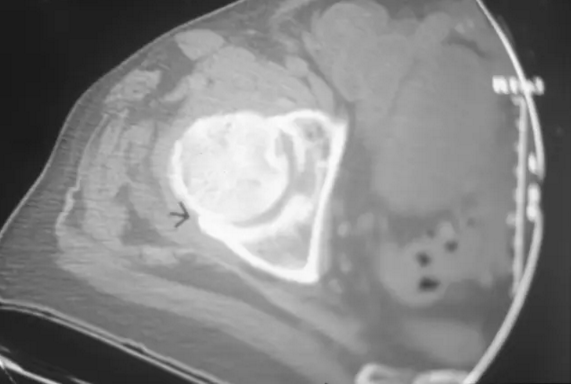

CT检查诊断股骨头缺血坏死较X线片敏感,可早期发现微小的病灶、软骨下骨板微骨折等,对于股骨头缺血坏死的分期有着重要的意义,根据CT检查所见进行分期较X线片更准确。

对股骨头缺血坏死的患者CT显示股骨头的前部的骨折。 这个发现在轴向脂肪饱和的T2加权磁共振图像上被证明,但是由于CT扫描的优异的分辨率,使用CT扫描更清楚地描绘。

该患者病程6个月,患者经过了骨内减压术后,但已经股骨头已经可以看到的轻度扁平化,表明尽管已经治疗,病情还是有进展。

该患者病程6个月,患者两侧缺血坏死,经过了骨内减压术后,右侧股骨头近端已经轻度扁平化,这表明疾病从阶段2到阶段3的进展,尽管保守治疗。 右侧近端股骨头内的缺陷代表死骨的移除。